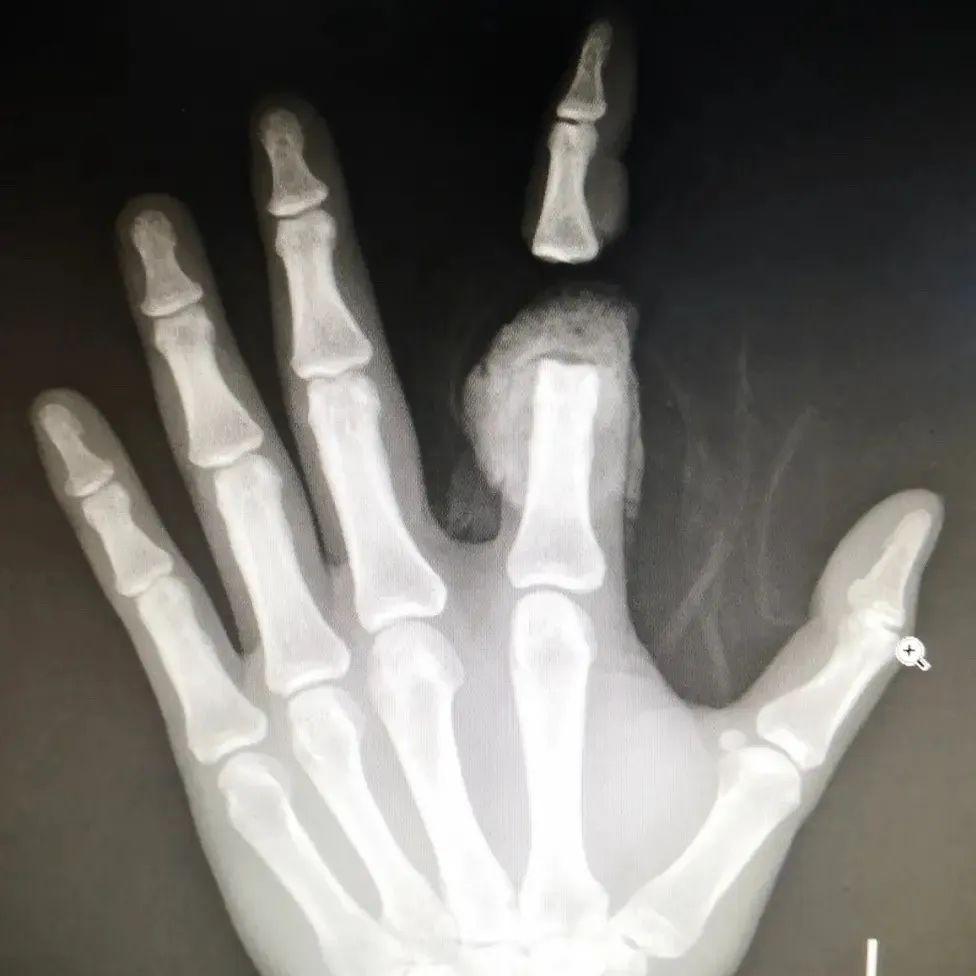

电锯锯断食指伤情危重 医生妙手完成断指再植

三秦都市报-三秦网讯(乔梦菲 记者 阮班慧)近日,患者强先生不慎被电锯割伤,导致食指自第一指节处完全离断,被紧急送至西安市长安区医院急诊科。患者伤情危重,创面极不规整,大量出血,并自行携带有离断指体。面对这一紧急情况,医院立即启动创伤救治绿色通道,急诊科及创伤病区团队紧密协作,成功为强先生实施断指再植手术,保住了其手指功能。目前,患者断指已确认成活,正处于功能恢复阶段。

患者抵达急诊科后,医护团队对其生命体征和伤情进行了快速、全面的评估,诊断为左手食指完全性离断伤,创面污染挫伤严重。对于离断指体而言,6-8小时内恢复指体血运是提高成活率的关键。团队争分夺秒安排各项术前检查,并同步通知创伤病区显微外科团队做好急诊手术准备。多部门高效联动,为后续手术争取了宝贵时间。

手术室内,一场与时间赛跑的精密手术在高倍显微镜下展开。麻醉成功后,团队首先对伤指进行彻底清创,对接骨骼,并细致修复受损肌腱。随后开始吻合细如发丝的神经与血管。然而,术中探查发现,由于电锯伤的特性,创面边缘极不规整,离断指体断端有一长段血管挫伤严重,无法直接吻合。面对这一突发情况,显微外科组当即调整手术方案,在与家属充分沟通后,决定实施“移花接木”——即从患者腕部选取管径合适的血管移植,以修复损伤血管,最终挽救断指。

手术由蔺秋麇主任与吕蒙医生等团队成员协作进行,蔺秋麇主任负责清除残肢异物,在保护缺损的血管神经的同时彻底清创、整理修复离断食指,使用骨圆针固定指关节骨骼后,探查血管,由深及浅依次修复关节囊、伸屈肌腱等。吕蒙医生则负责“移花接木”,将取自腕部的浅静脉移植桥接至食指双侧指固有动脉并进行精细吻合。经过3小时的紧张手术,断指再植顺利完成,术中血管通血良好。